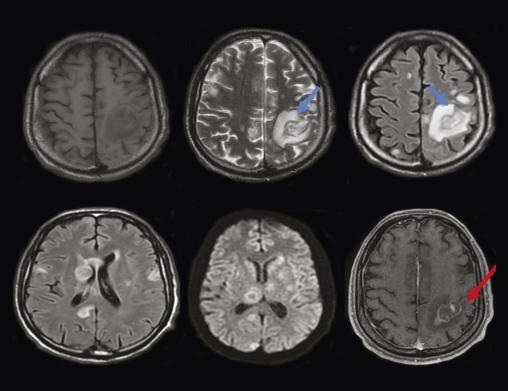

Un homme âgé de 51 ans, sans antécédents particuliers, a depuis deux semaines une hémiplégie droite et une dysarthrie évoluant dans un contexte d’apyrexie et d’altération de l’état général. À l’examen clinique, le patient, conscient, est stable sur le plan hémodynamique et respiratoire ; l’examen neurologique objective un déficit moteur de l’hémicorps droit. Les constantes sont les suivantes : température à 37,3 °C, pression artérielle de 125/75 mmHg, indice de masse corporelle (IMC) de 18,6 kg/m2. Le bilan biologique initial (hémogramme et protéine C-réactive) est normal. Le patient bénéficie en urgence d’une tomodensitométrie (TDM) cérébrale sans et avec injection du produit de contraste montrant des plages hypodenses éparses non systématisées avec prise de contraste annulaire après injection du produit de contraste (fig. 1 ). Par la suite, une imagerie par résonance magnétique (IRM) cérébrale caractérise ces multiples lésions parenchymateuses cérébrales sus- et sous-tentorielles en hypersignal T1, hypersignal T2 hétérogène, en hypersignal et Flair, avec une restriction sur la diffusion, se rehaussant en cible excentrée « target sign », avec œdème périlésionnel (fig. 2 ). Face à cet aspect radiologique, le diagnostic de toxoplasmose cérébrale est évoqué. Puis une sérologie toxoplasmique et au virus de l’immunodéficience humaine (VIH) se révèle positive, avec un taux de CD4 de 89 cellules/mm3. Le patient est traité par un antiparasitaire (pyriméthamine avec acide folinique) associé à une trithérapie antirétrovirale. Malgré une prise en charge rapide, l’évolution est marquée par une aggravation du tableau clinique, avec installation de troubles de la conscience ayant conduit au décès.